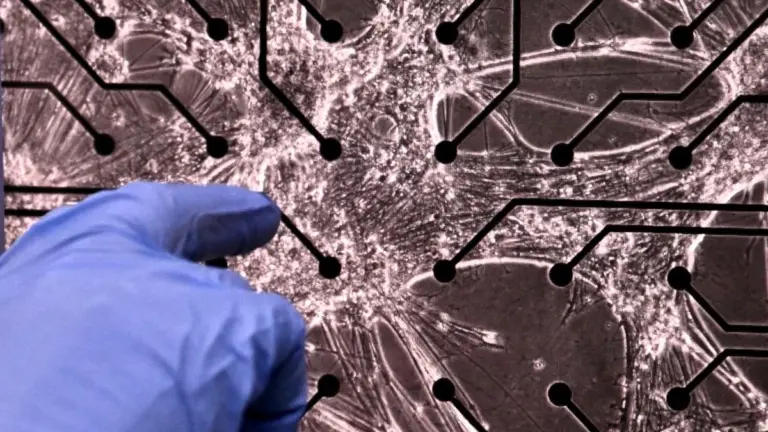

V čem byl tento výzkum jiný? Vědci se zaměřili na specifickou část mozku:

- Sledovali takzvané bazální ganglia, která řídí motoriku.

- Použili technologii DaT SPECT, která se běžně používá jen u seniorů.

- Zkoumali mladé dospělé ve věku 18 až 24 let, tedy desítky let před obvyklým nástupem nemoci.

Při skenování mozků 12 mladých lidí s autismem vědci narazili na něco překvapivého. U třetiny z nich vykazovaly transportéry dopaminu nenormální chování. To znamená, že proces „recyklace“ dopaminu u nich nefungoval standardně. Zajímavé je, že tito lidé přitom neměli žádné problémy s IQ nebo motorikou, které by je odlišovaly od ostatních.